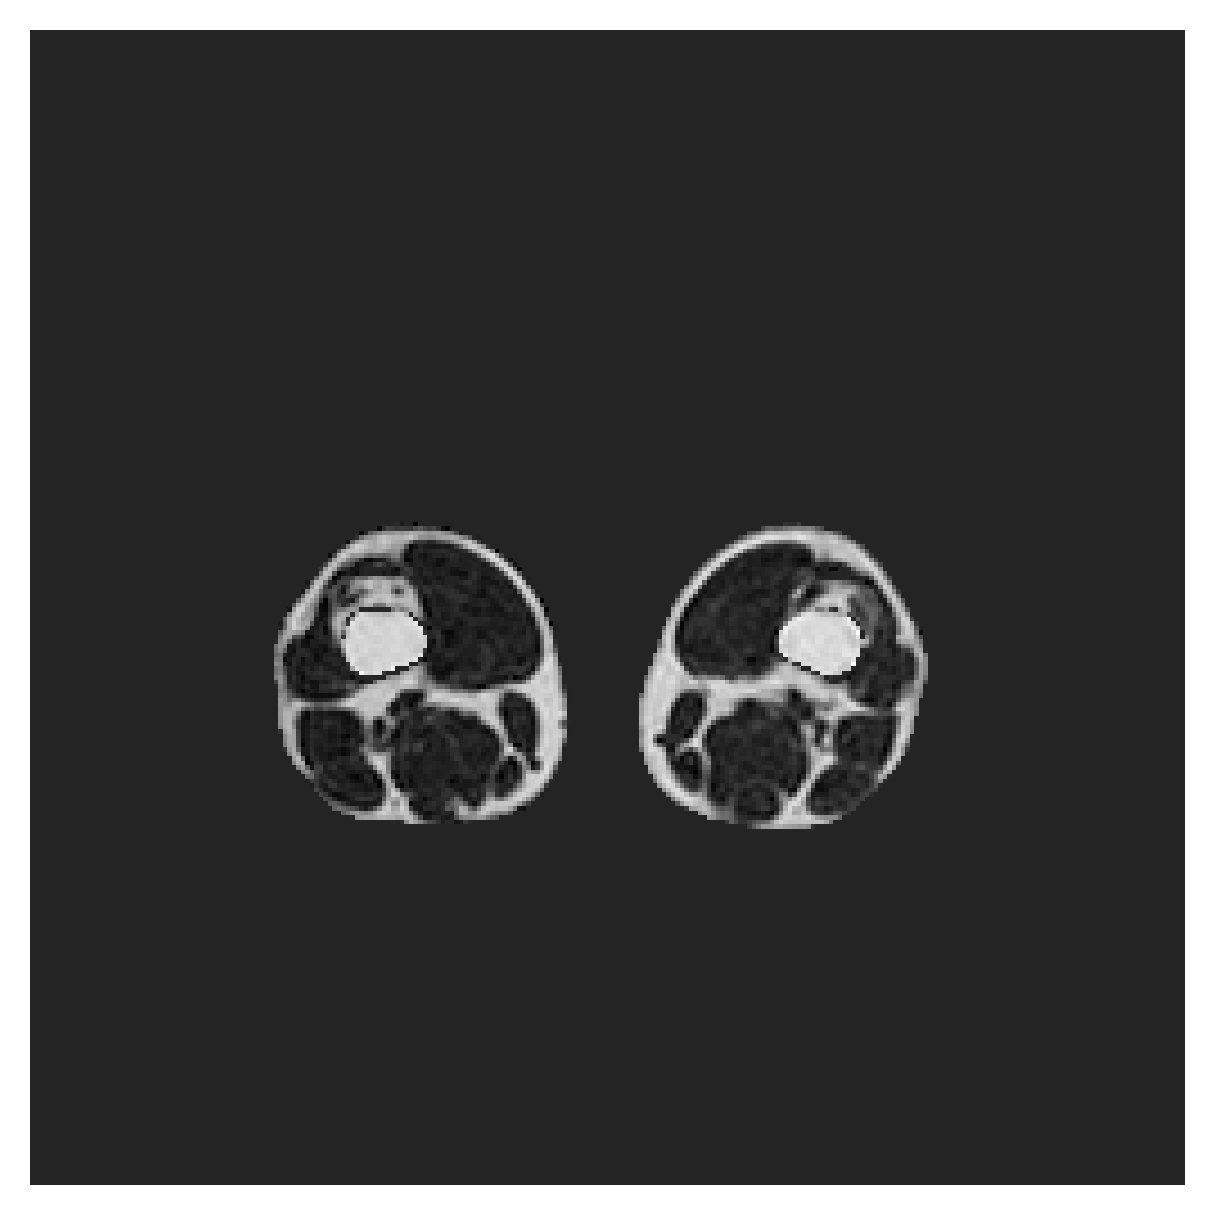

We normalize the volumes and resize the slices to pixels. As the official dataset comes with full annotations, we create a synthetic point ground truth. This is done by first randomly choosing the centers of the point annotations within the class masks, followed by filling an ellipse with axes lengths of and (in pixels) around each center. The intersections of these elliptic discs with the underlying full annotations are then used as our point ground truth. See Figure 2 for an example of the created weak annotation mask. The point annotations are created for every slice, one for each foreground object present in the slice.